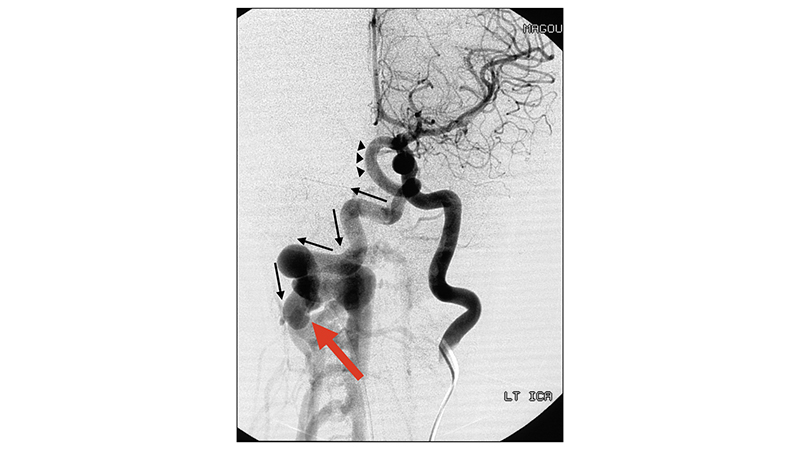

Η φλεβική παροχέτευση γίνεται με διάταση του συστήματος της δεξιάς οπισθίας σφαγίτιδος φλέβας με συμφορηση των παρασπονδυλικών εξωσκληρίδιων φλεβών. - Εκλεκτική αγγειογραφία της αριστερής έσω καρωτίδος αρτηρίας σε προσθιοπίσθια λήψη. Διά μέσου της οπισθίας αναστομωτικής αρτηρίας με αναστροφή της ροής στην βασική αρτηρία (αιχμές μαύρων βελών), και την δεξιά σπονδυλική αρτηρία (μαύρα βέλη), διακρίνεται η σπονδυλο-σπονδυλική επικοινωνία (κόκκινο βέλος). Υπάρχει λόγω αναστροφής της ροής στσπονδυλοβασικό σύστημα, υποκλοπή στην αιμάτωση των στοιχείων του οπισθίου κρανιακού βόθρου.